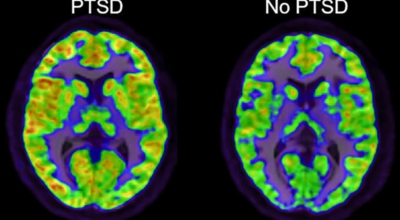

우리 인체 기관 중 뇌 부근에 해마와 편도체라는 것이 존재한다고 합니다. 여기에서 공포나 불안 등이나 스트레스를 제어하는 기능을 한다고 하며, 이 기능을 정확하게 하지 못해 문제가 발생되는 것이라 합니다. 인체에 심한 스트레스가 발생 시 편도체가 흥분이 되고 스트레스 호르몬인 코티졸이라는 것이 발생될 수 있습니다. 이 물질은 해마라는 기억 관련 기능을 담당하는 기관에 좋지 않은 영향을 미치고, 이로 인해 어떤 외상에 연관하여 정확한 기억을 하기 보다는 부분적이고 좋지 않았던 부정적 기억만 남아 스트레스를 유발할 수 있다고 합니다.